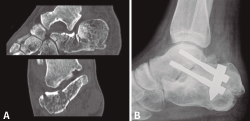

Tras estudiar la posible correlación entre diferentes variables, encontramos que de los 25 pacientes tratados de forma conservadora el resultado fue excelente-bueno en el 68% de los casos, mientras que de los 22 tratados con placa de reconstrucción el 95,4% obtuvieron resultados clínicos valorados como excelentes-buenos. La mitad de los tratados con tornillos canulados percutáneos presentaron resultados favorables y en el caso del sistema Vira® el 80% tuvo resultados excelentes-buenos. En la Figura 3 se muestra un caso tratado quirúrgicamente con este sistema.

Figura 3. Caso tratado con artrodesis primaria. A: tomografía de fractura de calcáneo de tipo III AB; B: resultado posquirúrgico mediante artrodesis primaria con clavo Vira®.